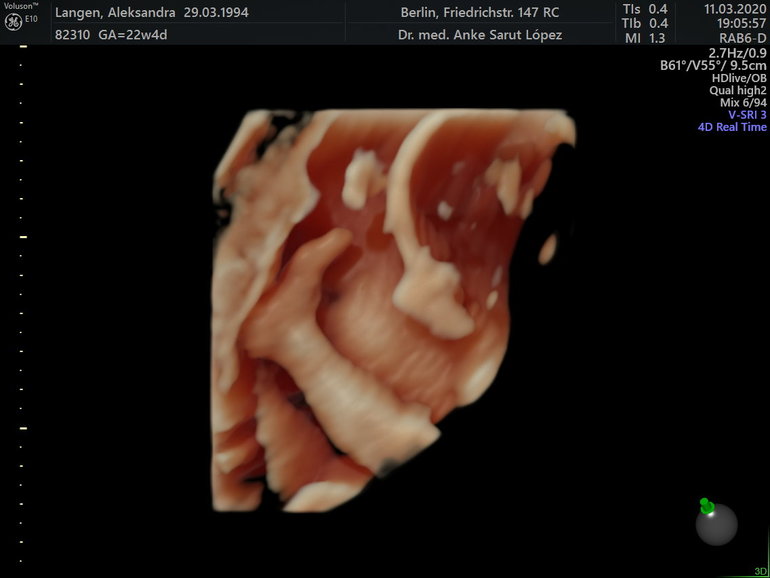

Срок беременности 22 недели и 4 дня, малыш весит примерно 512 грамм.

Все органы в порядке, все показатели в пределах нормы. Переживала за длину шейки, сказали 34,5мм...угрозы преждевременных родов нет, кровоток хороший, плацента сзади.

Малыш активничает, вчера толкался сильно и часто, я всё гадала чем он так сильно толкается и вот тайна открыта 😂: